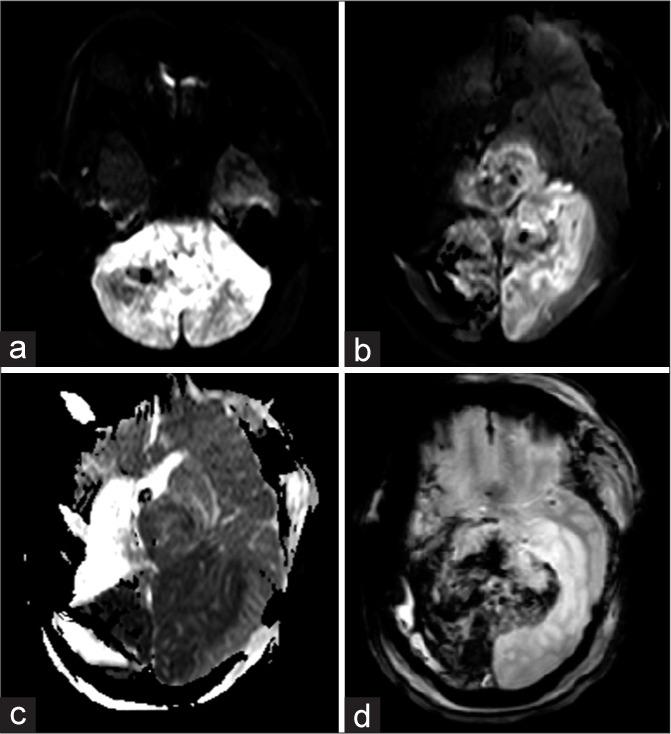

A 52-year-old gentleman with a 210 mL volume and middle cerebral artery territory infarction underwent an emergency craniectomy and 6 months later a titanium mold cranioplasty. Precranioplasty computed tomography (CT) scan evaluation revealed a sunken skin flap with a 9 mm contralateral midline shift. Immediately following an uneventful surgery, the patient had sudden fall in blood pressure to 60/40 mmHg and over a few min had dilated fixed pupils. CT revealed severe diffuse cerebral edema in bilateral hemispheres with microhemorrhages and expansion of the sunken right gliotic brain along with ipsilateral ventricular dilatation. Despite undergoing a contralateral decompressive craniectomy due to the midline shift toward the right, the outcome was fatal.

一名52岁男性,脑梗死体积为210 mL,累及大脑中动脉供血区,接受了急诊颅骨切除术,6个月后进行了钛模颅骨修补术。颅骨修补术前的计算机断层扫描(CT)评估显示皮瓣凹陷,对侧中线移位9 mm。手术顺利完成后,患者血压突然降至60/40 mmHg,几分钟内瞳孔散大固定。CT显示双侧半球严重弥漫性脑水肿,伴有微出血,右侧凹陷的胶质化脑膨出,同侧脑室扩张。尽管因中线向右移位而进行了对侧减压性颅骨切除术,但结果仍为死亡。